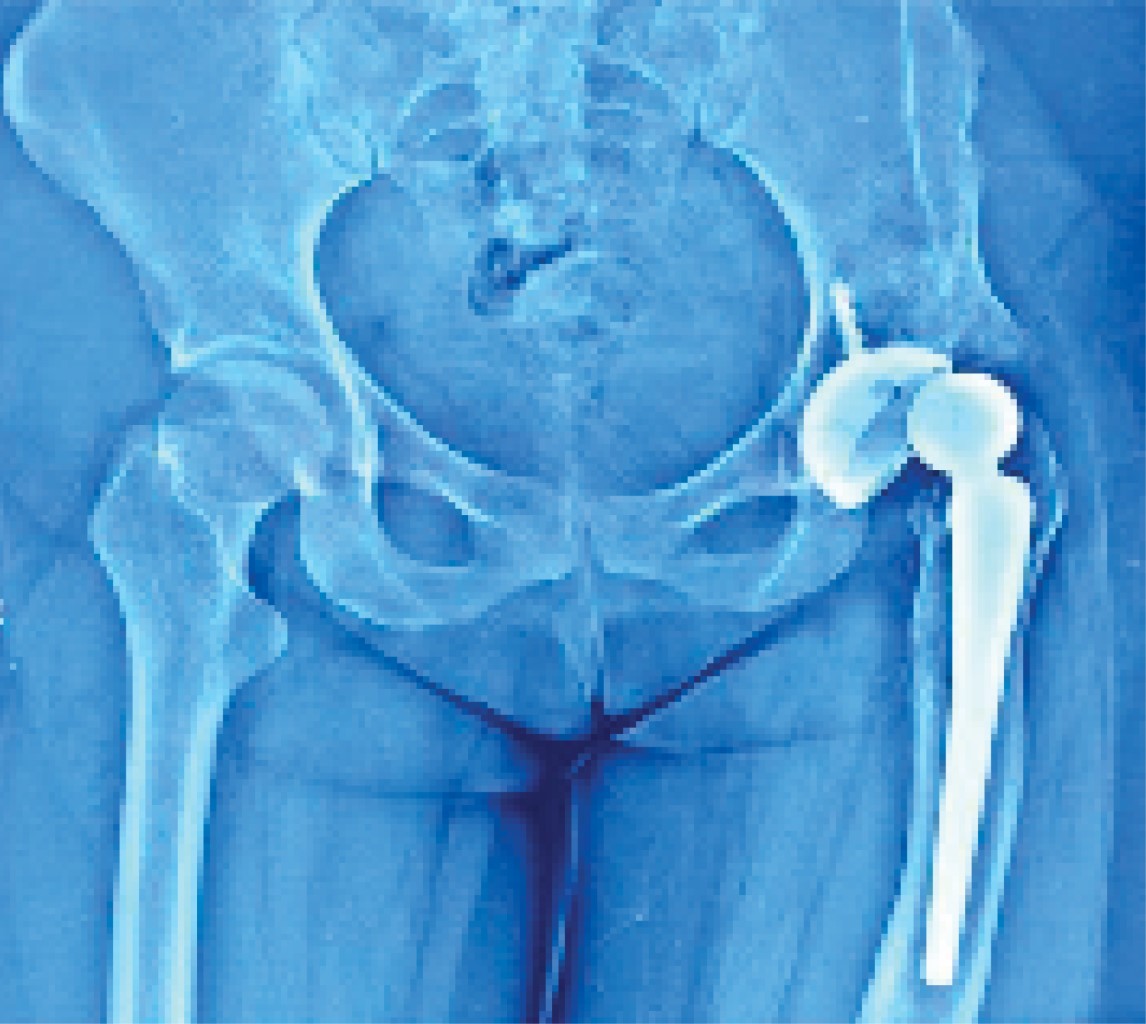

Mujer de 26 años con antecedentes de displasia del desarrollo de la cadera izquierda manejada quirúrgicamente durante la infancia con osteotomía de pelvis y osteotomía desrotadora de fémur, las cuales fueron fallidas (Figura 1), presentando secuelas en el desarrollo de su cadera durante su adolescencia con artrosis secundaria (Figura 2), con intenso dolor y limitación a la movilidad, impidiendo sus actividades cotidianas, motivo por el que se le realiza artroplastia total de cadera en clínica privada en el año 2017 a sus 22 años (Figura 3).

En 2018 a sus 23 años acude a mi consulta, refiriendo que continúa con dolor y limitación a la movilidad de la cadera protésica, a la exploración física se encuentra un acortamiento de extremidad inferior izquierda de 3 cm, así como limitación en los arcos de movilidad, se realiza radiografía anteroposterior de pelvis observando subluxación de prótesis total de cadera izquierda, con inadecuada colocación de componentes articulares.

Figura 3